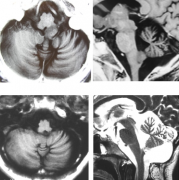

延髓膠質(zhì)瘤是絕癥嗎能治好嗎?延髓是膠質(zhì)瘤中較不常見(jiàn)的位置,包括局灶性背外生性、局灶性、彌漫性和頸髓連接變異。頸部延髓腫瘤通常代表向上延伸...